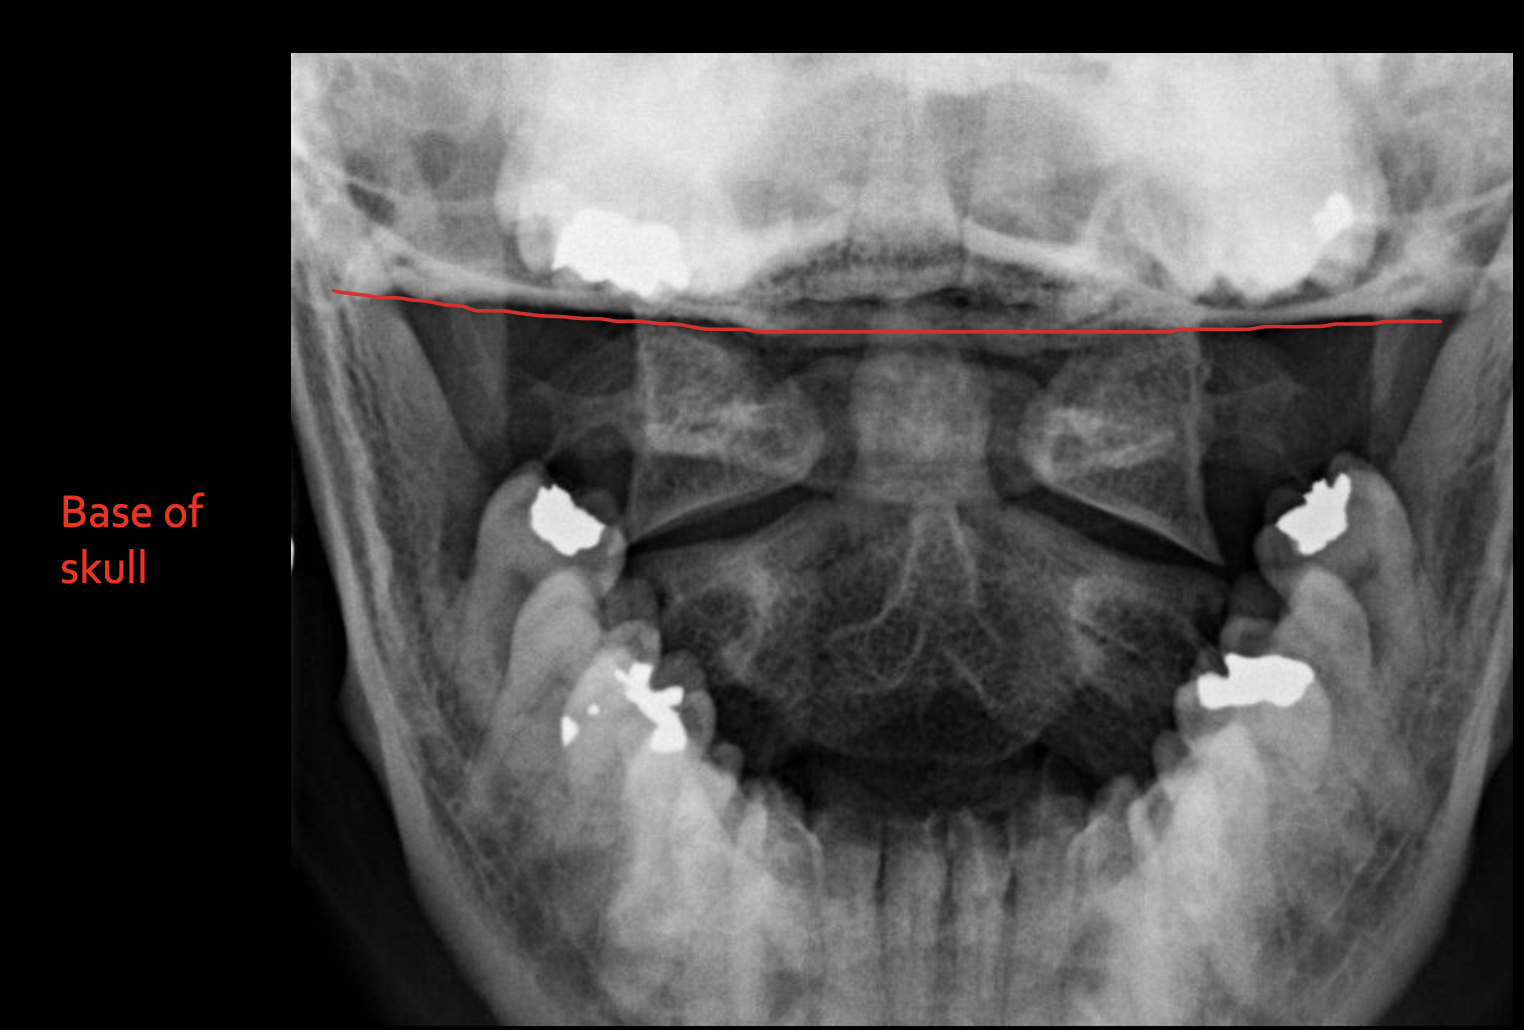

颅底

Base of skull